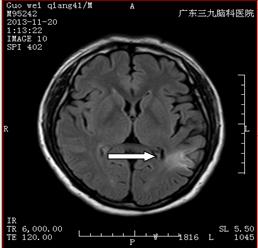

【典型案例二】

谭某,男,64岁,因反复头晕、感觉天旋地转1个多月至广东三九脑科医院治疗。

入院后,医生为其完善了所有检查,头颅MRI提示双侧小脑半球、桥脑右侧多发软化灶形成伴胶质增生、局限性脑萎缩,考虑脑梗塞后遗改变(图一);PWI-ASL提示双侧小脑半球、桥脑右侧低灌注(图二);DSA检查显示右侧颈内动脉起始部重度狭窄、狭窄程度大于90%,长 约5mm;2.右侧椎动脉开口中度狭窄,程度约45%,长约3mm,其余脑血管未见明显异常(图三)。

术前MRI(图一) 术前ASL(图二)